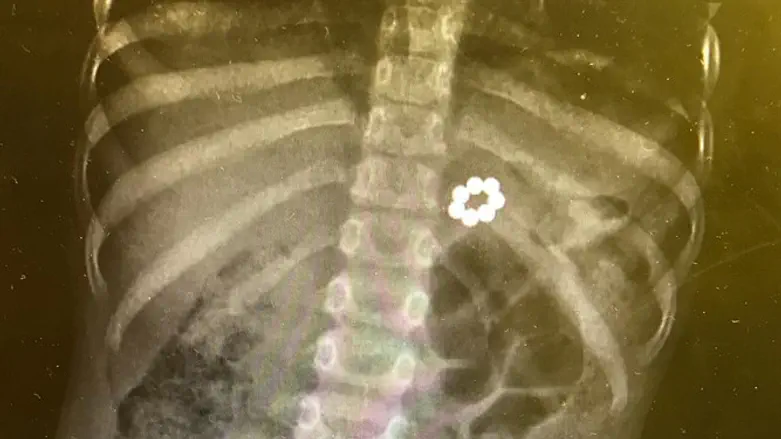

''הוצאת החרוזים הייתה מעט מסובכת במקרה הזה ודרשה שיקוף בזמן אמת. התקדמנו לאט לאט עד שהוצאנו את כל החרוזים מהמעי של הבחור הקטן, בסה"כ שבעה מגנטים'', תיאר הרופא.